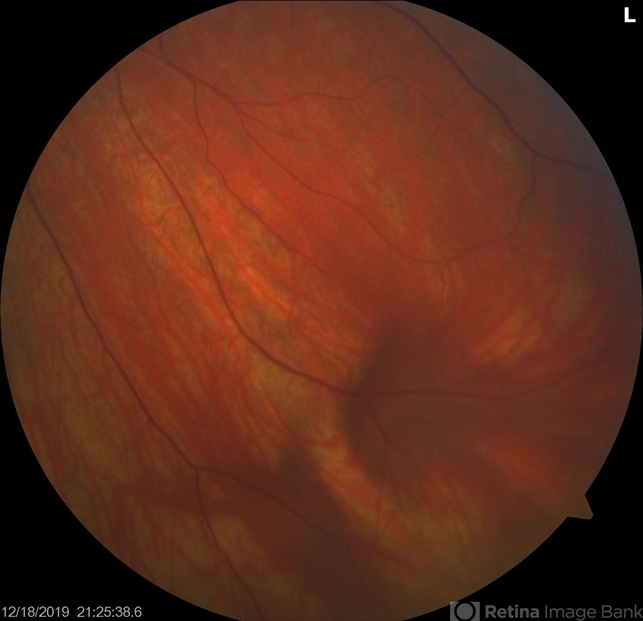

- retinal varices, vortex vein

- There is a prominent vortex vein ampulla. Typically these are present in in the inferior nasal quadrant when the eye is directed toward the vessel. It is benign and not to be confused with a mass lesion. Reassured patient. Varices OU. Prominent Vortex Vein Ampulla. Recommended observation.